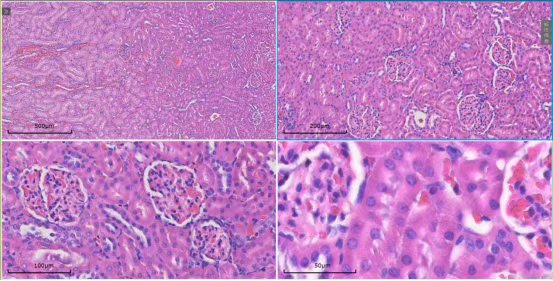

扫描系统覆盖4倍、10倍、20倍及40倍等多个物镜倍数。无论是在4倍镜下观察组织全貌,还是切换至40倍油镜分析细胞亚结构,系统均能确保图像清晰、细节无损,为形态学定量分析给予可靠依据。

针对超大尺寸切片,系统可自动进行图像采集与无缝拼接,生成完整的全景数字切片。研究者可在全景图中快速定位,并直接放大至目标区域进行高倍数观察,实现“整体布局-局部特征”的一体化分析。

该服务专注于给予系统性的扫描方案,尤其适用于心脏、肝脏、脾脏、肺脏及肾脏等主要器官的组织切片。

以肾脏研究为例,该服务还可给予全景扫描与多切面对比的特色解决方案,以满足深度研究需求。

肾全景 横切-纵切